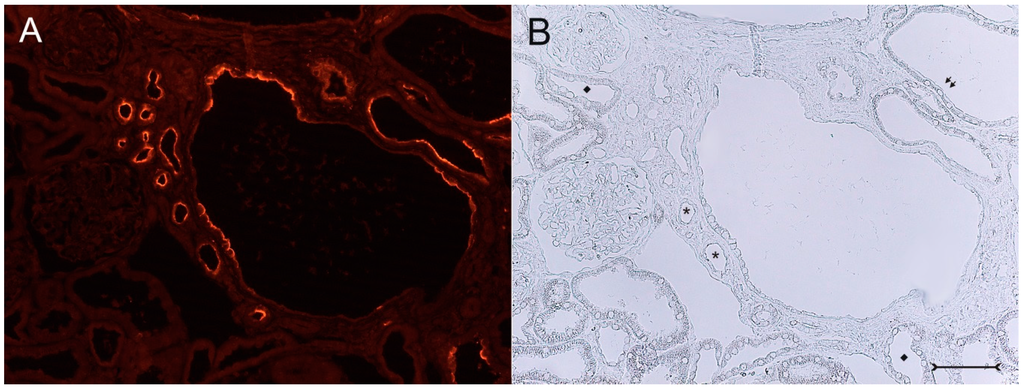

In adult (cy/+) kidneys, a distinct immunohistochemical Kim-1 expression can be seen in several tubular, partly cystic structures of the kidney cortex and outer stripe (Figure 1A), whereas no Kim-1 expression is found in the corresponding areas of wildtype (+/+) kidneys (Figure 1B). Western blot analysis confirmed the exclusive expression of Kim-1 in (cy/+) kidney extracts, whereas no bands were identifiable in (+/+) kidneys (Figure 2).

A closer view of (cy/+) kidney cortical structures confines Kim-1 labeling to epithelial cells of proximal tubular profiles, which demonstrated a complete loss or massive reduction of their brush borders (Figure 3A,B). Within cystic proximal tubules, Kim-1 is expressed either by scattered or some coherent cells or in agglomerated cell clusters of the cyst wall, while in others, a large majority of cells of a given profile were Kim-1 positive as within atrophic proximal tubuli (Figure 3A). Kim-1 immunoreactivity demonstrated a distinct apical cell distribution (Figure 3A). In addition, Kim-1 is also expressed in parts of hyperplastic cysts with an apical and lateral cell staining pattern (Figure 4A,B). In well-developed brush borders of proximal epithelia expressing the proximal differentiation marker aquaporin-1 (AQP-1), virtually no Kim-1 is expressed, but in neighboring profiles undergoing atrophy, a mixed picture is apparent in double labeling experiments with cells co-expressing both Kim-1 and AQP-1, or only either protein, or even neither protein (Figure 5A–C). Of note, in areas of apparently normal non-dilated proximal tubules, sporadically individual cells exhibit an apical Kim-1 expression (see also Figure 5). No relevant expression of Kim-1 could be revealed in distal nephron segments nor in other regions by carefully analyzing multiple sections. However, some dilated thin descending limb (TDL) profiles, found only in the outer stripe and being AQP-1-positive, were also Kim-1-reactive (Figure 6A–C). These profiles may also represent dilated end portions of S3 proximal tubules. Double labeling experiments with Kim-1 and calbindin-D28k, which labels distal convoluted tubule (DCT) and connecting tubule (CNT) profiles in the cortical labyrinth excluded the expression of Kim-1 in these segments (Figure 7A–C). Thick ascending limbs (TAL) and collecting ducts (CD), identified by their histomorphology, were devoid of signals for Kim-1.

Figure 3. Kim-1 immunohistochemistry with fluorescent staining (A), (cy/+) rat kidney cortex; (B) corresponding phase contrast image. A mosaic-like expression pattern of Kim-1 in cyst wall epithelia of a large cyst (in the middle) with apically-concentrated labeling is seen; virtually all cells of this cyst are devoid of a brush border and show different morphologies. Small atrophic proximal tubuli (examples are marked with stars in (B)) in the vicinity of the central cyst are Kim-1 positive, have markedly lost their brush borders and are surrounded by a compacted, fibrosed interstitium. Distal tubules (examples are marked with diamonds in (B)) are devoid of a signal. Parts of the cystic profiles with a maintained brush border (see arrows, upper right in (B)) do not express Kim-1. Bar = 75 µm.